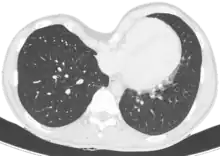

Coupe au scanner.

Le diagnostic est clinique, par l'examen de la déformation thoracique. On peut toutefois proposer la réalisation d'une tomodensitométrie thoracique, permettant le calcul de l'index de Haller, évaluant de manière objective la sévérité de la déformation et permettant de rechercher une compression cardiaque, trachéale ou œsophagienne. Des explorations fonctionnelles respiratoires évaluent l'impact de la déformation sur la fonction pulmonaire, et une épreuve d'effort recherche l'impact sur les capacités d'effort.